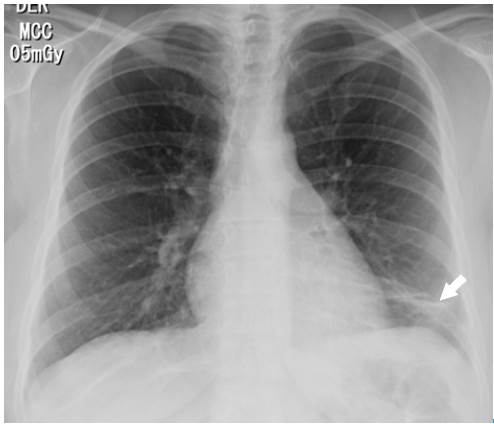

Surprisingly, after initiating anticoagulation and other general treatment measures indicated for pulmonary thromboembolism, and about three days after her hospitalization, the patient required increased oxygen flow through nasal cannula, her chest pain worsened, and presented with dyspnea, fever, leukocytosis, tachycardia, and tachypnea. Control para-clinical exams were requested, revealing high C-reactive protein and a significant increase in leukocytes at neutrophils expense. A new chest tomographic evaluation was performed, in which wedge densities were identified in the middle and lower right lobes and in the lower left lobe, as well as an aerial bronchogram of the right lower lobe and bilateral pleural effusion (Figure 3 and 4). No blood cultures or sputum cultures were performed.

Chest AngioCAT. Broad base consolidation, hilar apex, obtuse borders that coincide with pulmonary infarction (star), pleural effusion (arrow).

Fig 4: Chest AngioCAT. Broad base consolidation, hilar apex, obtuse borders that coincide with pulmonary infarction (star), pleural effusion (arrow).